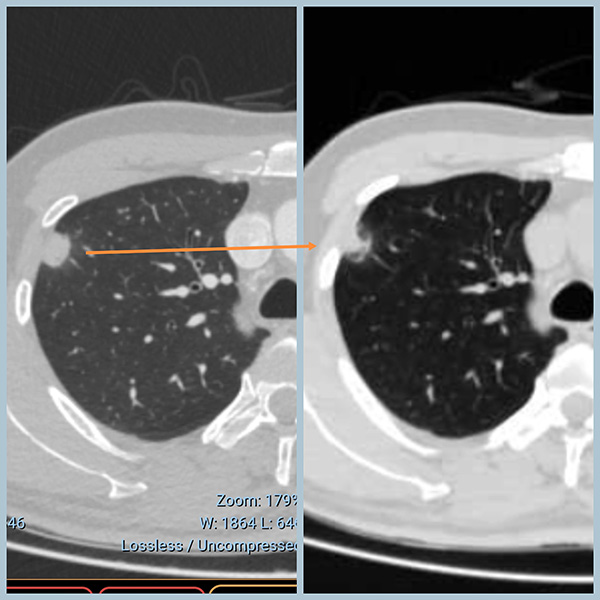

一个月后复查:病灶明显吸收、变小!不是恶性!

两次CT对比,变化(缩小吸收)一目了然!

1、庆幸自己有追问最早片子的习惯。不管患者出于何种原因没有同时拿出两次CT,单看后一次CT,确实也像炎症,但没有前面的对比,印象不会这么深刻。

2、感叹给出抗感染建议的医生水平之高。他可能基于患者的年龄,肺门多发的钙化淋巴结,肺上其它钙化点等考虑有炎症可能。但是如果我是初诊医生,看到这个病变(消炎前)可能还是首先考虑恶性,基于30多岁的年纪,我可能会让患者做PET或穿刺明确诊断。